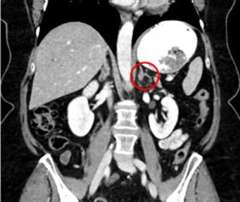

When patients have images taken of their abdomen with a CT scan or MRI, it is very common to see an adrenal nodule. In fact, we see adrenal nodules in 4 out of every 100 people that get a CT or MRI. An adrenal nodule is when normal tissue grows into a lump. Most incidental adrenal nodules do not cause health problems. However, they need to be evaluated for signs of excess hormone production or suspicion of malignancy. Because we often find adrenal nodules or masses when we were not looking for them, doctors will informally call these “incidentalomas.”

An incidentally discovered adrenal mass is a growth on the adrenal gland that is discovered "by accident" on a scan (typically at CT scan or MRI of the abdomen) performed for another reason, such as abdominal pain. As the availability and speed of scanners in developed countries increased from the 1980s onward, people received more and more scans, leading to the growing discovery of adrenal masses. The prevalence of incidental adrenal masses has varied from 0.5% to 7% in different studies. We know that older people are more likely to have incidental adrenal masses. Most of them are unilateral (just on one side) and most are benign, nonfunctional tumors (adenomas) that do not require surgery. However, up to 30% of incidental adrenal masses may require surgery, depending on (a) whether the mass is overproducing a hormone, or (b) whether there is concern for a malignant/cancerous mass.

Adrenal masses can overproduce several types of hormones, such as cortisol (causing Cushing's syndrome), aldosterone (causing hyperaldosteronism), and catecholamines (pheochromocytoma). Blood and/or urine tests measuring levels of these hormones should usually be performed in patients with incidentally discovered adrenal masses. The most common type of hormone overproduction in these tumors is mild autonomous cortisol secretion (MACS, formerly known as subclinical Cushing's syndrome). Depending on the imaging characteristics, such as size and density (the quantity of x-rays absorbed by a structure on CT scan), your doctor may recommend either removal of the adrenal mass or continued monitoring. Larger masses, such as those >4 cm (1.6 in) and those with high density (>10 Hounsfield units) are more concerning, whereas smaller adrenal masses and those with low density (<10 Hounsfield units, compatible with fat tissue) are less concerning.

There are some characteristics that are concerning for adrenal cancer: when the mass has irregular borders, when the tumor is bigger than 4 cm, when there are enlarged lymph nodes, nearby, and when we can detect distant metastases. Distant spreading ACCs generally metastasize to the lungs, liver, bone, and lymph nodes. It remains controversial, however, whether functioning or nonfunctioning tumors are more aggressive.